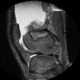

Arthritis with joint effusion

A joint effusion is the presence of increased intra-articular fluid. It may affect any joint. [Source: Wikipedia ]